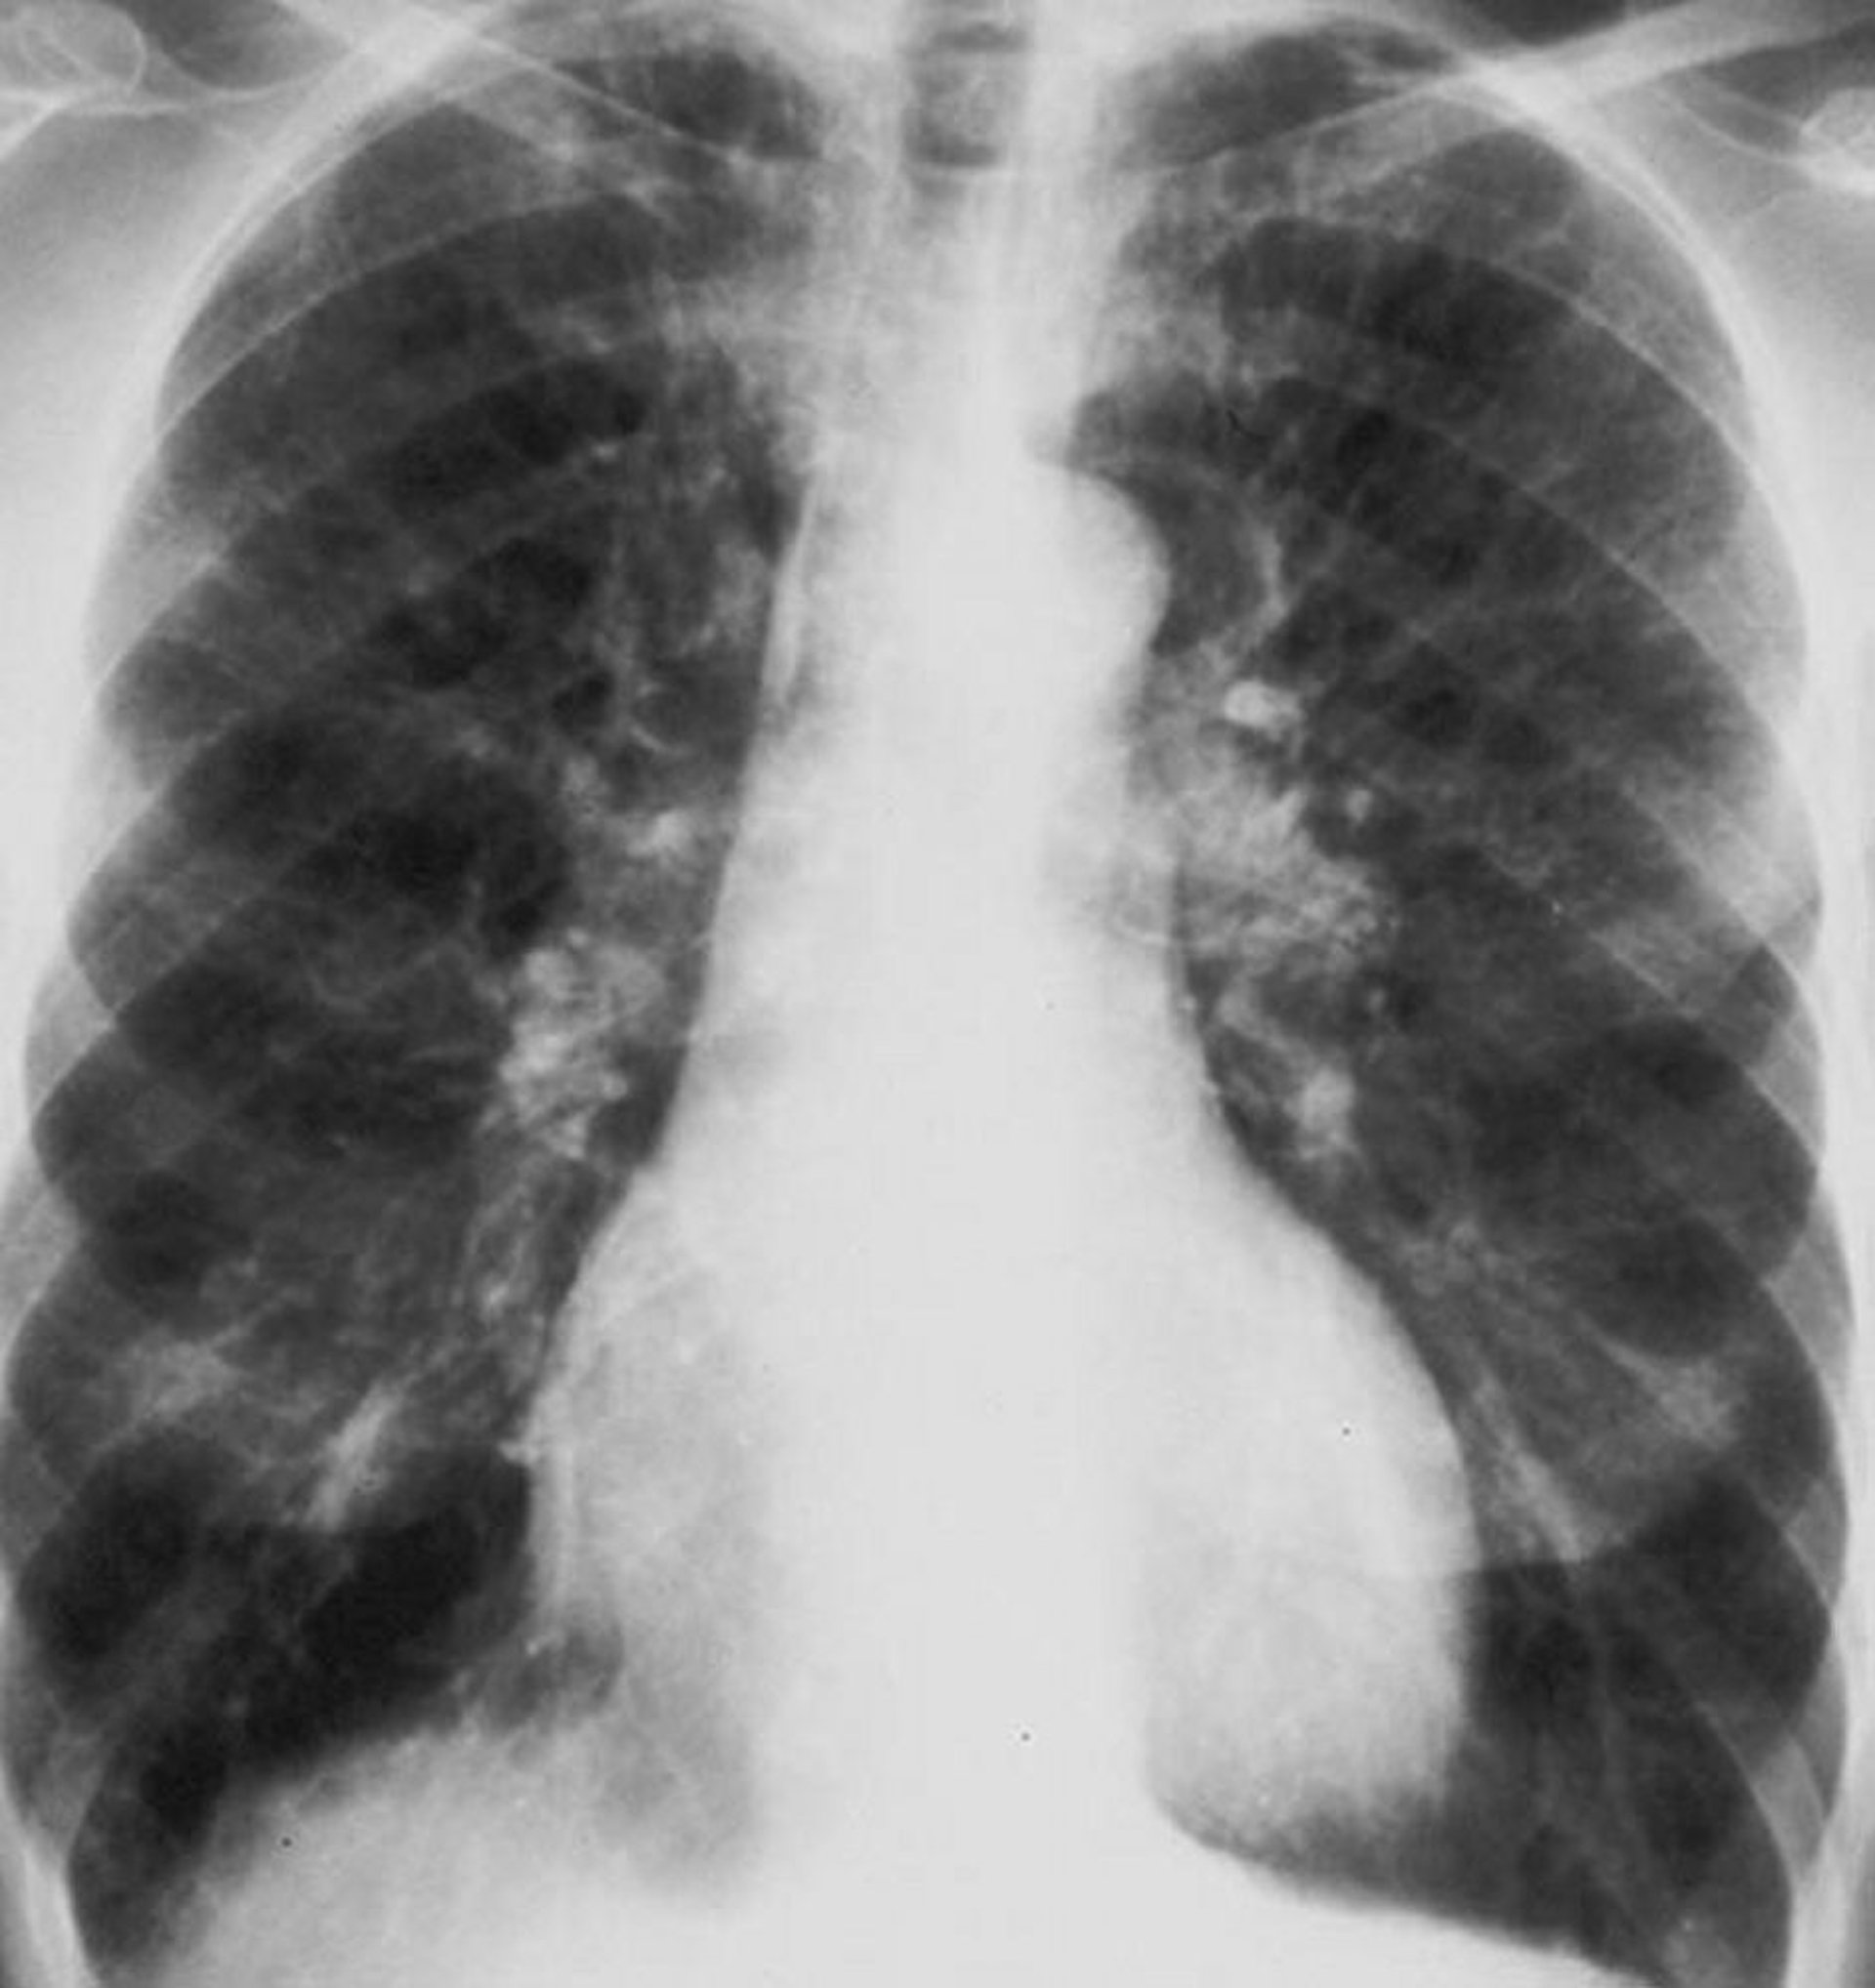

Broncopneumopatia cronica ostruttiva (radiografia del torace)

Radiografia del torace di un paziente con broncopneumopatia cronica ostruttiva. I polmoni sono iperinflati, il diaframma è appiattito, vi è accentuazione vascolare e la dimensione del cuore è leggermente aumentata.

By permission of the publisher. From Barnes P. In Bone's Atlas of Pulmonary and Critical Care Medicine. Edited by J Crapo. Philadelphia, Current Medicine, 2005.